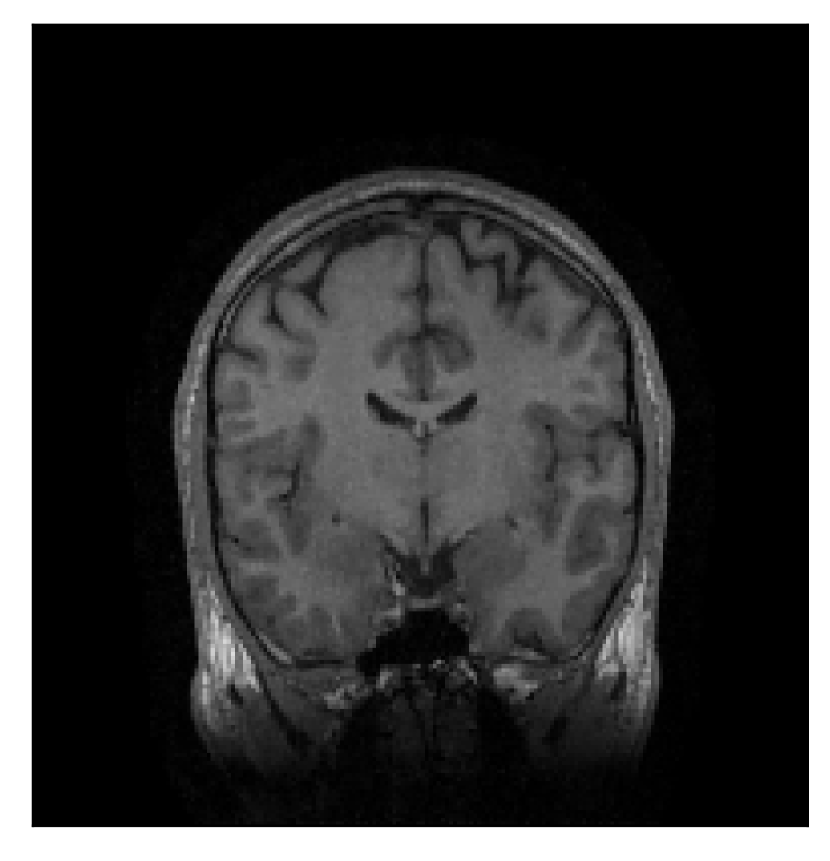

4.1 Experiment 1: robustness test

We gather the results for the robustness test described in Section 3.1 (volunteer 1) in Figures 2, 4, and 6 for motion corruption mechanisms associated to one, two, and five changes of position, respectively. Furthermore, we juxtapose the corrected images with varying degrees of corruption in Figure 8. We observe that the proposed method consistently ameliorates the corrupted scan. The quality indexes based on PSNR and SSIM show only a modest decrease in correction quality as a function of motion complexity (Figure 8).

| Section 3.1, Figure 2 | Sagittal | 23.94 | 27.95 | 0.7068 | 0.7936 |

| Coronal | 26.66 | 29.82 | 0.7653 | 0.8332 | |

| Axial | 25.40 | 30.16 | 0.7616 | 0.8490 | |

| Section 3.1, Figure 2 | T2-FLAIR | Completely corrected | Some blurring | No additional artifacts | Good grey white matter differentiation |

| Section 3.1, Figure 4 | T2-FLAIR | Completely corrected | Some blurring | No additional artifacts | Good grey white matter differentiation |